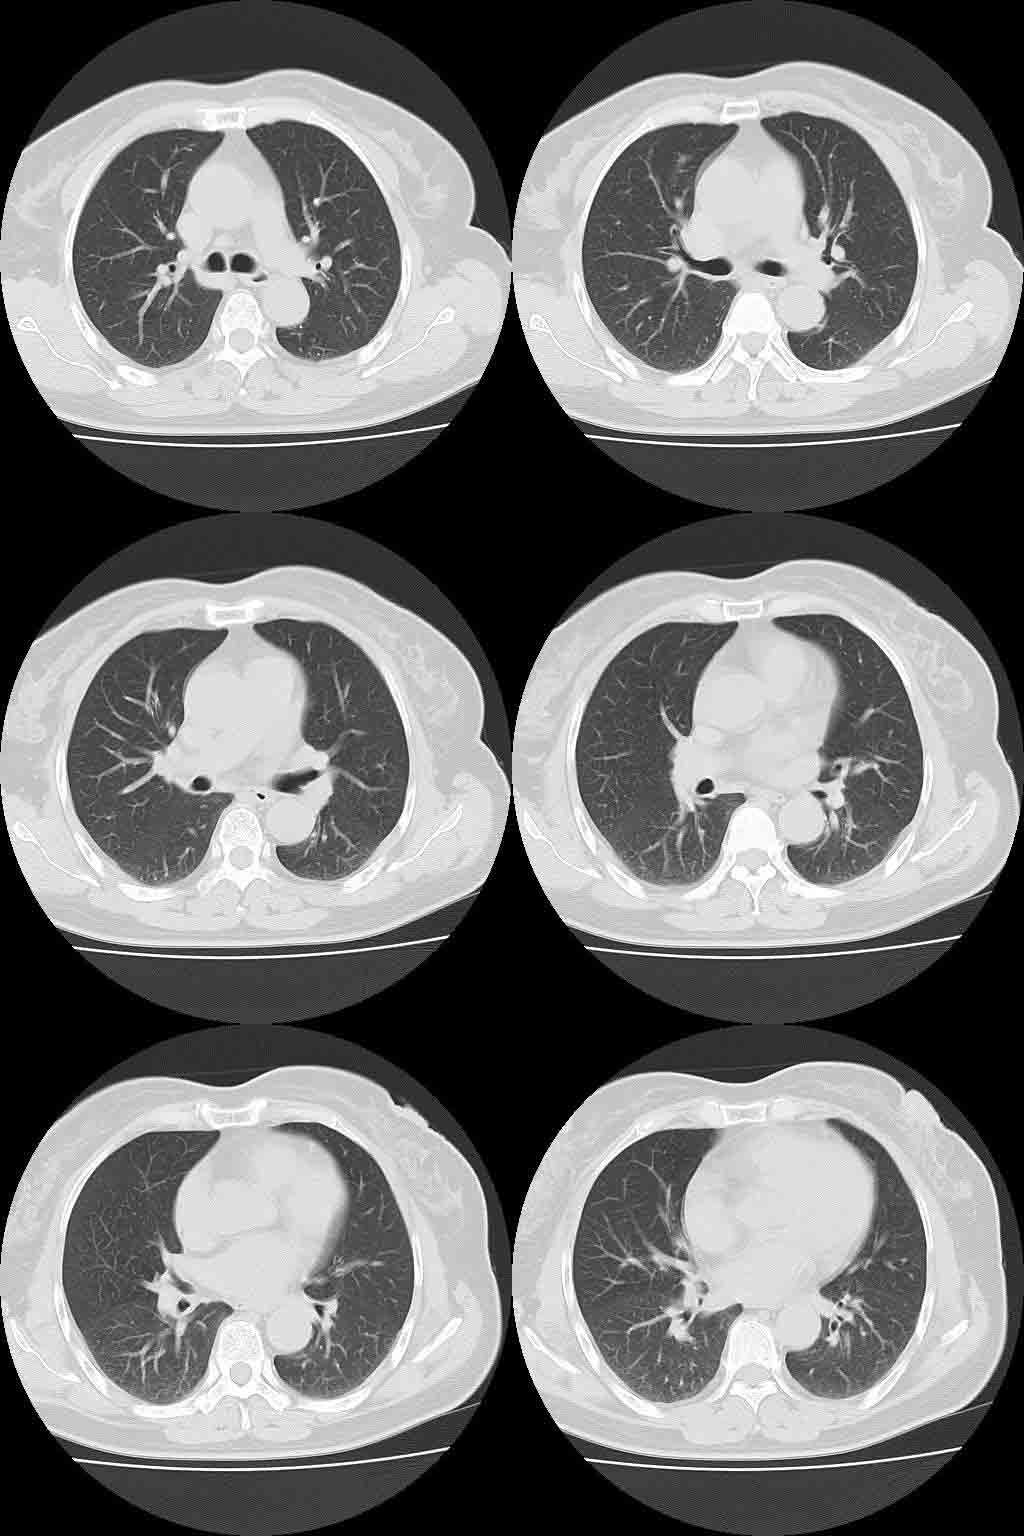

以下是引用lkc8963在2008-10-4 22:24:00的发言:[br]右下肺内基底段不规则软组织结块,肿瘤可能,建议增强鉴别于血管.